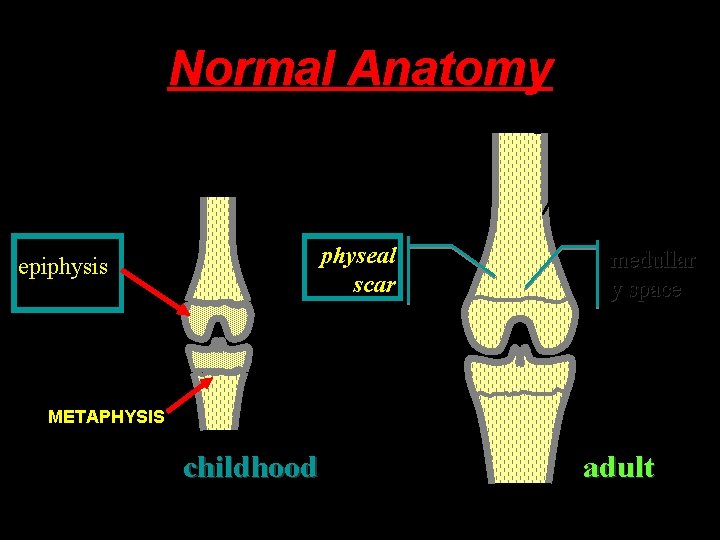

Normal Anatomy diaphysis cortex metaphysi s physeal physis scar epiphysis medullar y space METAPHYSIS childhood adult

Normal Anatomy diaphysis cortex metaphysi s epiphysis medullar y space physeal scar childhood adult